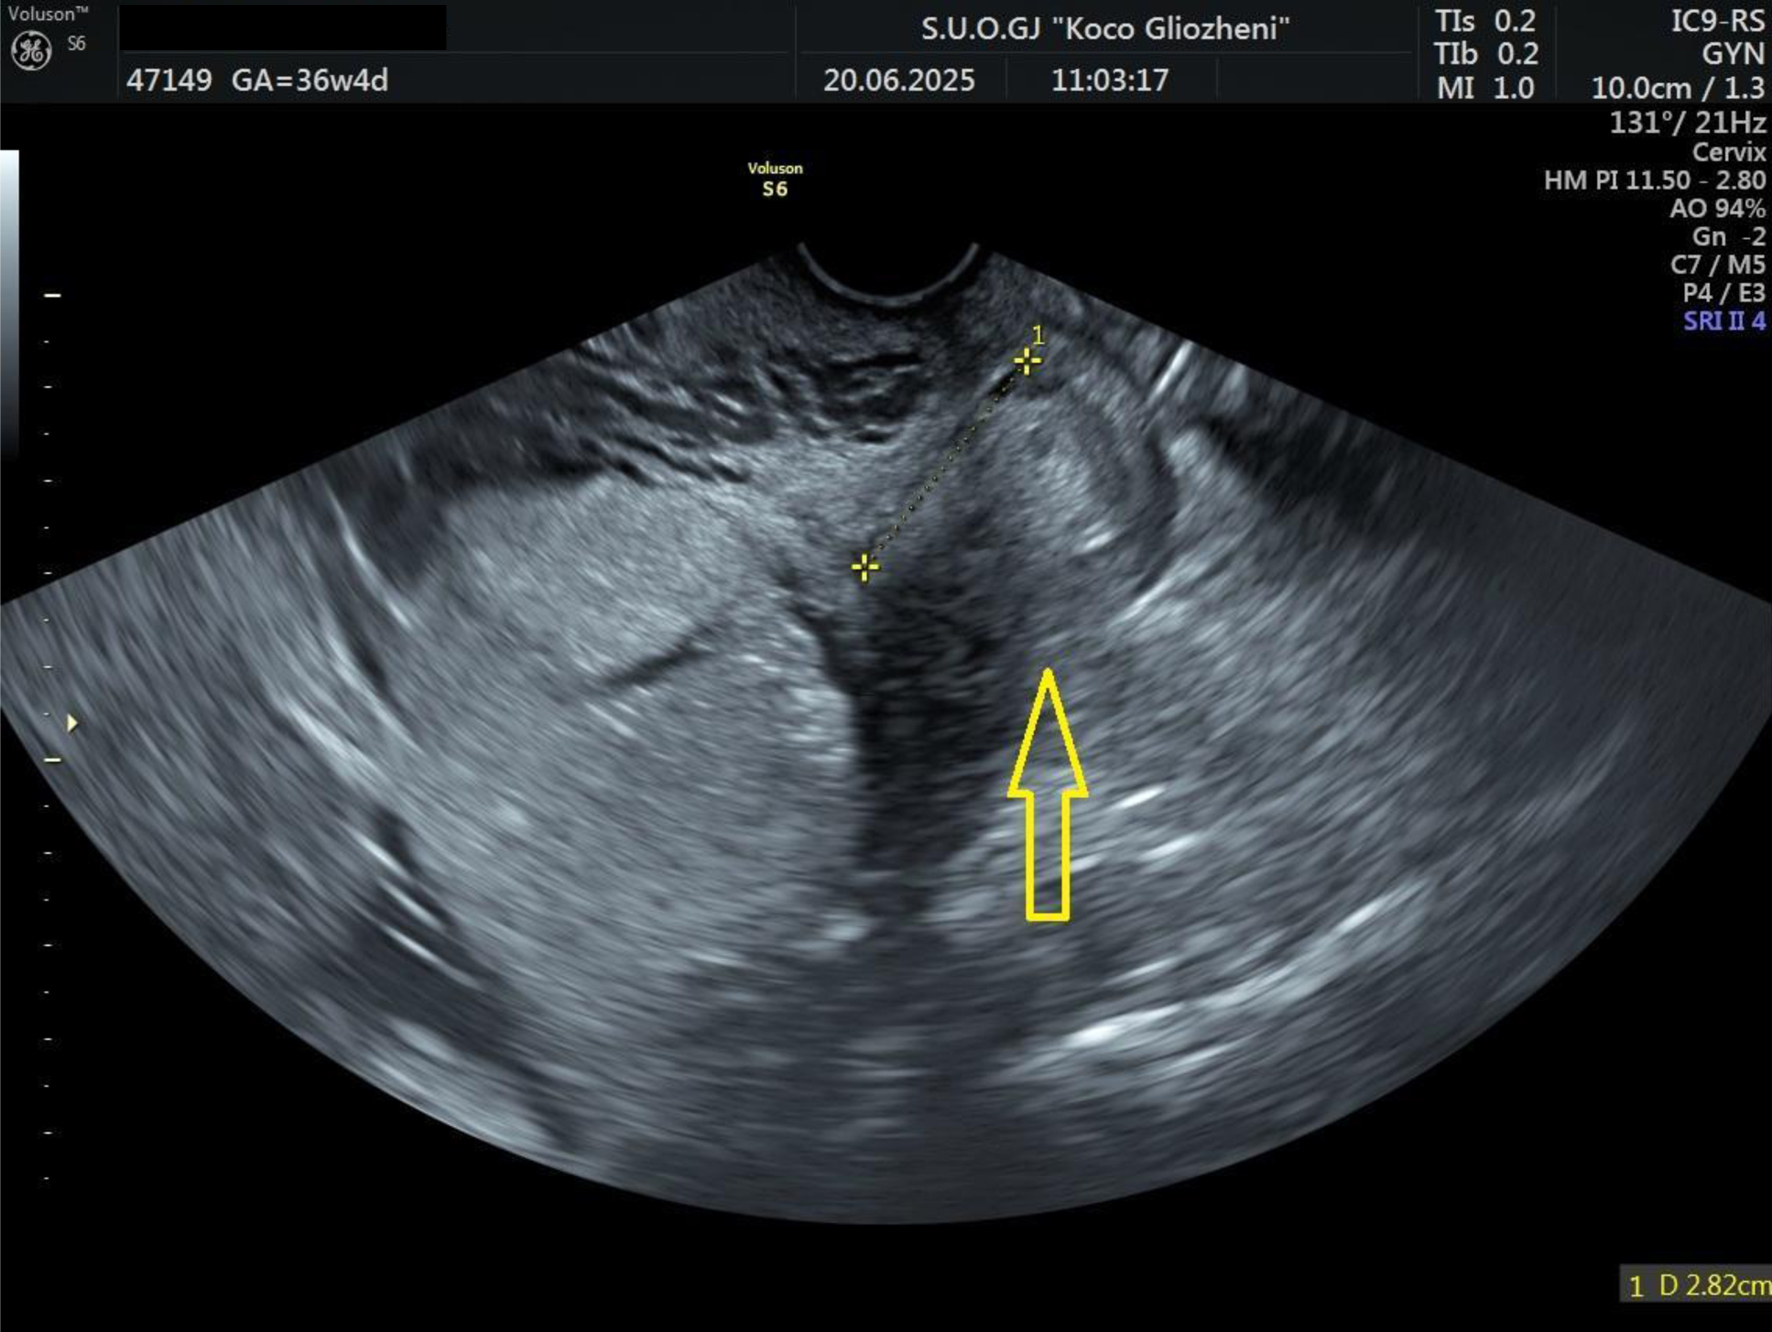

A 41-year-old woman at 36 - 37 weeks’ gestation, body mass index (BMI) 26 kg/m2, with a history of two prior cesarean deliveries and a transverse fetal lie, was admitted for evaluation. Ultrasound showed an anterior placenta completely covering the internal os, invading the full myometrial thickness up to the serosa, consistent with PAS, with marked Doppler vascularization (Figs. 1 and 2). So, elective cesarean section was indicated, and the blood bank was notified ensuring blood reserves. The surgical team was composed by obstetrician, vascular surgeon, and urologist.

Figure 1. Ultrasound examination showing placental tissue invading the lower myometrium (arrow).

Figure 2. Doppler ultrasound examination showing placental tissue invading the myometrium and extending to the serosa. Increased vascular flow was demonstrated on color Doppler ultrasound (arrow).